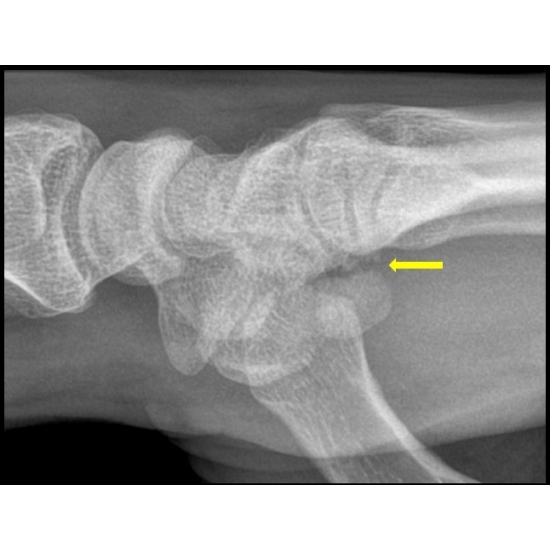

Three-view radiographs of the left hand and wrist were obtained prior to the clinic visit and reported as negative for acute fracture Case Photo #1 . After evaluation in clinic, radiographs were re-examined, and there was suspicion for a fracture at the base of the hamate Case Photo #2 , so a diagnostic ultrasound of the hand was performed. The ulnar artery Case Photo #3 was found to be widely patent without aneurysm, and the ulnar nerve and its deep branch had normal fascicular architecture without swelling or other signs of injury Case Photo #4 . Evaluation of the hamate bone demonstrated a cortical irregularity at the base of the hamate hook with overlying hypoechoic area consistent with a hematoma Case Photo #5 . Subsequent preoperative computed tomography confirmed a transverse fracture across the base of the hook of hamate with 1-2 mm of distraction and faint callus formation Case Photo #6 .